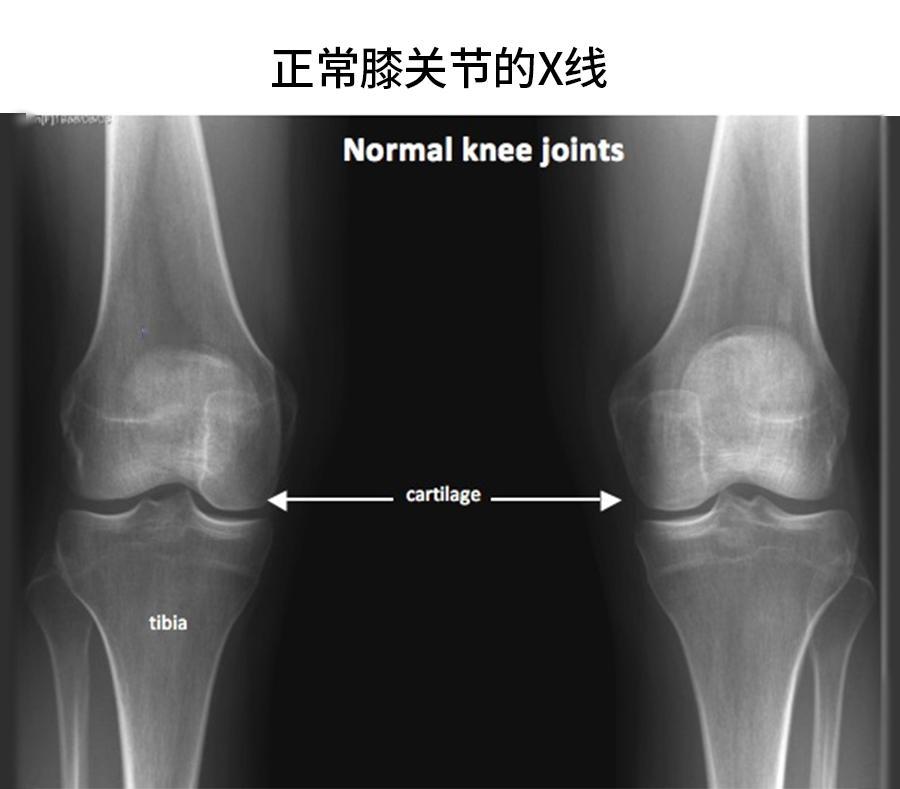

来看【正常】膝关节和【骨性关节炎】膝关节的片子——尤其是软骨,正常的膝关节,那条

来看【正常】膝关节和【骨性关节炎】膝关节的片子——尤其是软骨,正常的膝关节,那条线/面是很平滑的,但关节炎的那张,就是曲曲折折不规则的